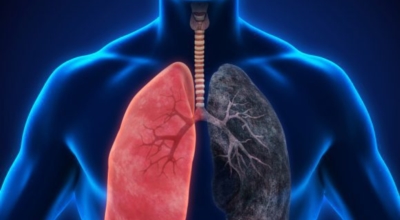

폐암의 공통 위험요소로 손꼽히는 이유가 되는 것으로 흡연이 있답니다. 흡연자는 비흡연자에 비교해 십몇 배는 더 폐암 발병확률이 높다고 하며 어느정도 기간 동안 흡연했는지에 따라 폐암 발생확률은 더더욱 더 높아져요. 흡연자라고 해도 금연을 하게 되면 폐암 발병확률이 빠르게 내려간다고 하니 폐암이 걱정되신다면 가장 먼저 금연은 필수입니다.

간접흡연 외에도 공사장과 같은 곳에서 미세먼지나 석면, 비소, 라돈, 카드뮴 등 신체에 옳지 않은 성분에 노출되는 환경적 요인으로 폐암이 발병할 수 있다고 하며 유전적 요인으로도 폐암이 발병할 수 있다고 해요. 가족 중 폐암을 앓았던 분들이 있다면 그렇지 않은 분들에 견주어 2배 가량 더 폐암에 걸릴 확률이 높다고 하는데요 이렇듯 폐암은 나도 모르는 새에 발병할 수 있으므로 자신의 신체 상태를 빈번히 체크하여 폐암을 초기에 발견하는 것이 현명해요.